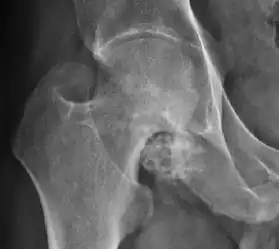

In adults, one of the main indications for radiographs is the detection of osteoarthritic changes (Figure 1(e)). Nevertheless, radiographs usually detect advanced osteoarthritis that can be graded according to the Tönnis classifications. The grading system ranges from 0 to 3, where 0 shows no sign of osteoarthritis. Intermediate grade 1 shows mild sclerosis of the head and acetabulum, slight joint space narrowing, and marginal osteophyte lipping. Grade 2 presents with small cysts in the femoral head or acetabulum, moderate joint space narrowing, and moderate loss of sphericity of the femoral head. Grade 3 is the severest form of osteoarthritis, which manifests as severe narrowing of the joint space, large subchondral cyst with productive bone changes that may lead to deformity of the bone components of the joint, while secondary osteoarthritis due to calcium pyrophosphate deposition can be diagnosed when calcification of hyaline cartilage and fibrocartilage is detected.[1]

There are other pathological conditions that can affect the hip joint and radiographs help to make the appropriate diagnosis. Acute bacterial septic arthritis can be diagnosed by radiographs when a fast regional osteoporosis and destructive monoarticular process develops (Figure 1(f)). In case of tuberculous or brucella arthritis it is manifested as a slow progressive process, and diagnosis may be delayed.[1]

Synovial chondromatosis can be confidently diagnosed by X-ray when calcified cartilaginous chondromas are seen. However, other synovial proliferative processes, such as pigmented villonodular synovitis, require MRI for accurate diagnosis, although noncalcified synovitis can be suspected in radiographs by indirect signs, such as soft tissue swelling and/or erosions in the femoral head, femoral neck, or acetabulum (Figure 7).[1]

- Osteoarthritis